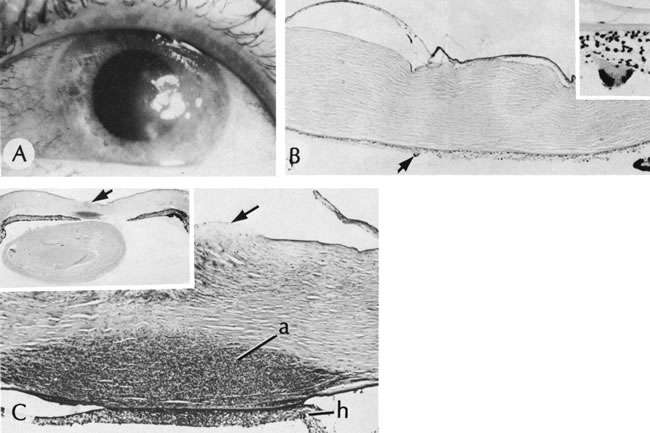

By light microscopy, eosinophilic intranuclear inclusions are characteristic of herpes simplex viral infections and represent the result of viral replication (Cowdri type A inclusions).121 Hypersensitivity type IV reactions in the stroma are characterized by lymphocytic and plasmacytic infiltrates. Intranuclear inclusions are relatively rare and are not found in most specimens. Viral particles occasionally can be found in multinucleated giant cells or within the stroma, especially in keratocytes (Figs. 20 and 21).

Fig. 20. Herpes simplex. A. Typical dendritic ulcer. B. Scanning electron micrograph of a dendritic ulcer in the epithelium of a rabbit cornea. C. Many intranuclear inclusions (arrows) are present in the corneal epithelium near the edge of the ulcer. D. Virus particles (arrows) of herpes simplex are present in the nucleus. E. Virus particles also are present within the cytoplasm. Note the large size of the cytoplasmic virions. Some particles show empty capsids, whereas others are complete, containing nucleoids. (Courtesy of SEI Photoarchives.) (B Courtesy of Dr. R. C. Eagle Jr; C from Font RL: Chronic ulcerative keratitis caused by herpes simplex virus. Arch Ophthalmol 90:382, 1973.)

Fig. 21. Herpes simplex. A. Clinical appearance of bullous keratopathy. B. Chronic condition shows development of bullous keratopathy. The anterior chamber inflammatory reaction contains multinucleated inflammatory giant cells (arrow), shown under high magnification in inset. C. Ulcerated bullous keratopathy (arrows). A corneal abscess (a) and hypopyon (h) are present. Note (inset) the subluxation of the lens to left, caused by the loss of zonula-lens attachments on the right, resulting in a “blunted” appearance of the right side of the lens. (Courtesy of SEI Photoarchives.)